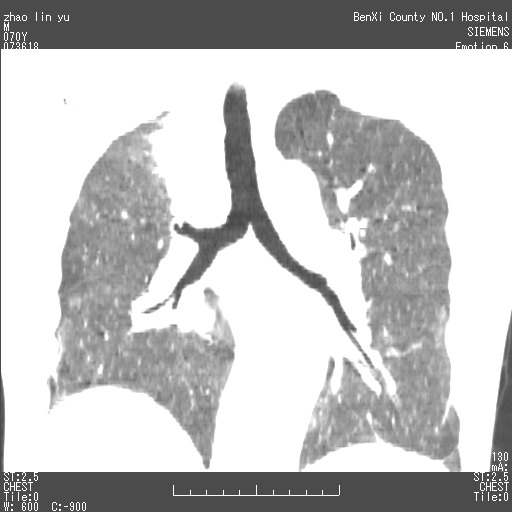

以下是引用王靖旗在2007-7-10 17:12:00的发言:[br] 男、70、咳嗽两个月,半年前换瓣手术,胸片未见异常,于昨天行x片发现右肺上野大片影,行ct扫描,这里是减薄图像,余肺正常。明天晚上会有增强扫描片,到时我会上传。[br][br] 冠状位请大家细看,应该是有意义的,[br][br] 请大家先看平扫发表意见。[br][br]

[br]冠状面[br]

以下是引用zhangzhongshou在2007-7-10 21:43:00的发言:[br]右肺上叶周围型肺癌,以孤立型细支气管肺泡癌可能性大。